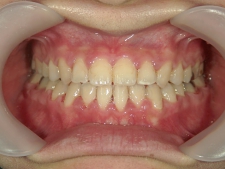

矯正歯科 治療後矯正歯科 全顎ワイヤー矯正 治療後矯正歯科(全顎ワイヤー矯正)治療後

矯正歯科 治療後

no.31_7964_治療後_右 .JPGno.31_7964_治療後_正面 .JPGno.31_7964_治療後_左.JPG